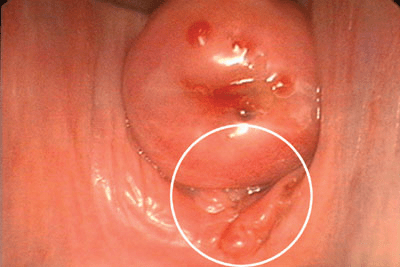

Il arrive qu’une patiente ait une endométriose visible dans le cul de sac vaginal postérieur (figure 2) qui est en fait la protrusion d’un nodule situé sur un ligament utéro-sacré ou sur le rectum. Il sera visible au cours de l’examen si le spéculum est orienté vers l’arrière. L’endométriose située sur une cicatrice de césarienne ou sur un ligament rond à sa sortie du canal inguinal se manifeste par des grosseurs douloureuses qui peuvent augmenter de taille pendant les règles.

Figure 2. L’endométriose du cul de sac vaginal postérieur a provoqué un amas épithélial (voir l’intérieur du cercle). Une endométriose vaginale peut être associée à une obstruction du cul de sac de Douglas et résulter d’une extension invasive de la maladie qui va des ligaments utéro-sacrés ou d’un nodule rectal vers le vagin.